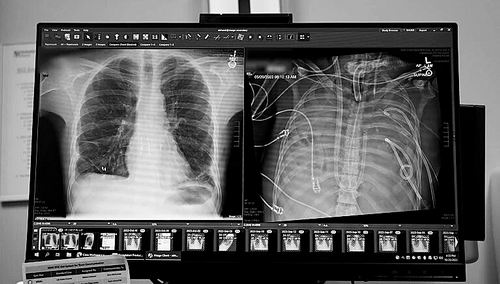

X光片显示的一名33岁患者的新肺(左)和旧肺。图片来源:美国西北大学

本报讯一名33岁的男子在没有肺的情况下存活了48小时。一个医疗团队用一套体外人工肺系统维持了这名男子的生命,直到他接受了双肺移植手术。1月30日,相关研究结果发表于《医学》。

令人惊讶的是,这名男子的病情很快有了好转。“在48小时内,他停止了所有维持血压的药物治疗,肾功能完全恢复,心脏也开始正常工作。”Bharat说。随后,该男子接受了双肺移植手术,也没有出现器官排斥或肺功能受损的迹象。“从我们进行这项手术到现在已接近3年,患者状况非常好。”